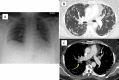

Figures